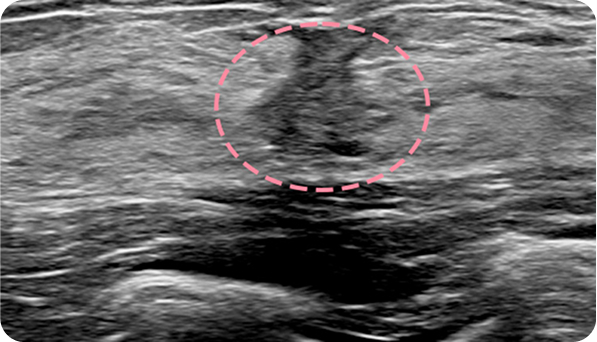

맘모톰시술 후 병리조직검사 결과 상피내암(조기 유방암) 초기로 진단되어 항암치료 없이 간단한 수술로 치료가 가능했습니다. 눈에 잘 띄지 않는 작은 병변까지 확인할 수 있었던 건, 맘모톰의 정밀한 조직검사 기능과 전문의의 정확한 판독이 있었기 때문입니다.